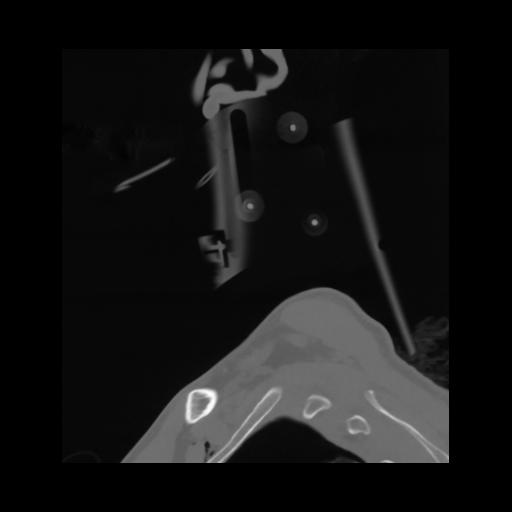

14 P.BLANDAS,,Sagittal,2.000,P.BLANDAS,Sagittal,